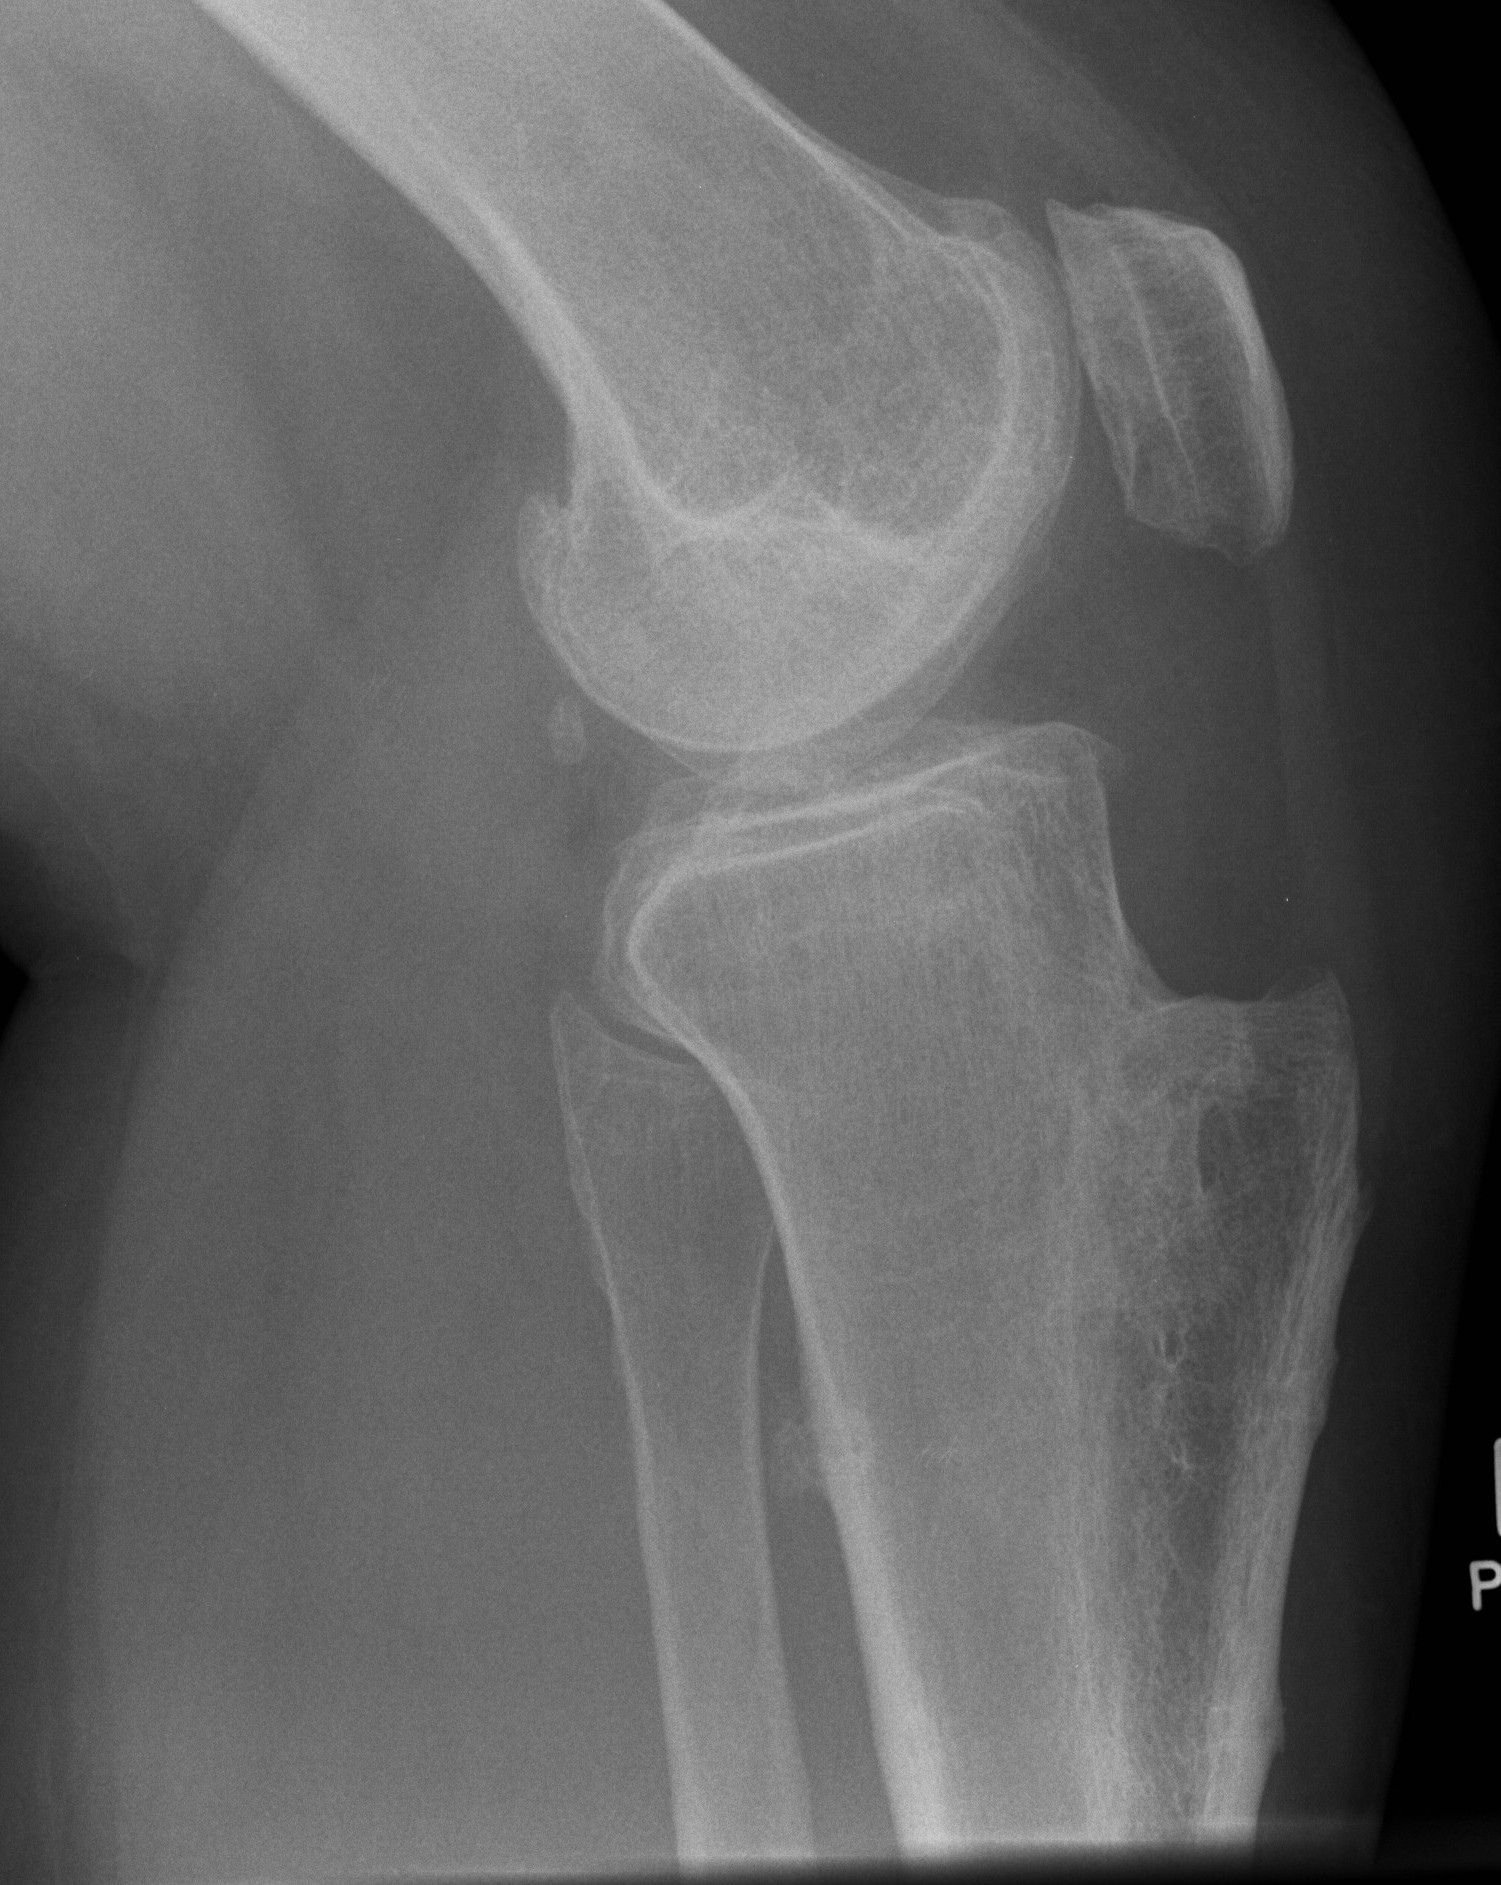

X-ray

Narrowing / osteophytes / sclerosis

Tilt / subluxation

Tilt Subluxation / osteophytes